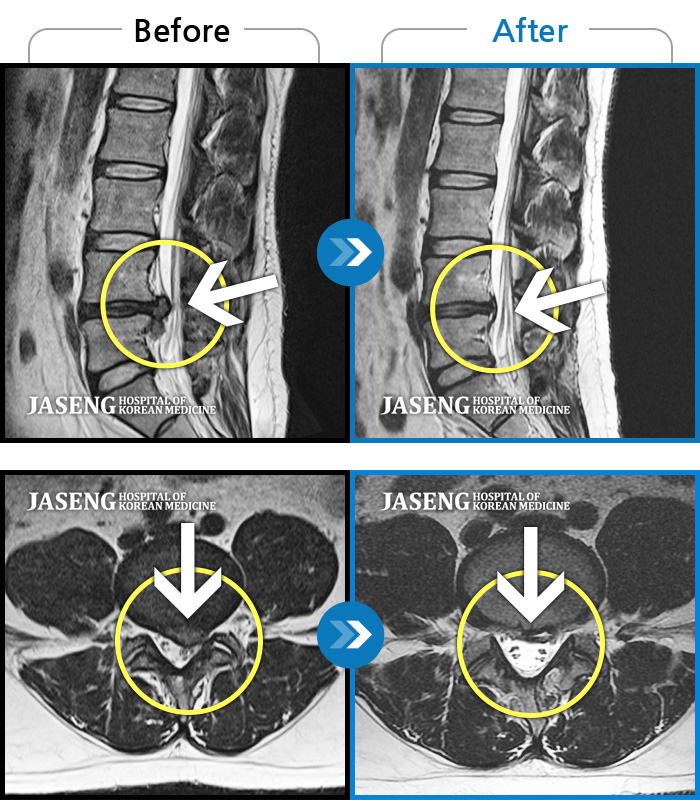

• 허리디스크